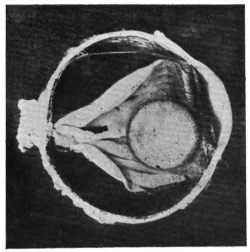

PLATE V.

28.

INJURIES TO UVEAL TRACT

curly bracket span

54

29.

FOREIGN BODY (TIP OF COPPER PROBE) IMBEDDED IN THE EYE

30.

TRAUMATIC DETACHMENT OF RETINA AND CHOROID

31.

WHOLE-SECTION OF FIG. 19

32.

PART OF THE ABOVE MAGNIFIED TO SHOW LENS IMBEDDED IN INFLAMMATORY EXUDATE

33.

PHAGOCYTOSIS